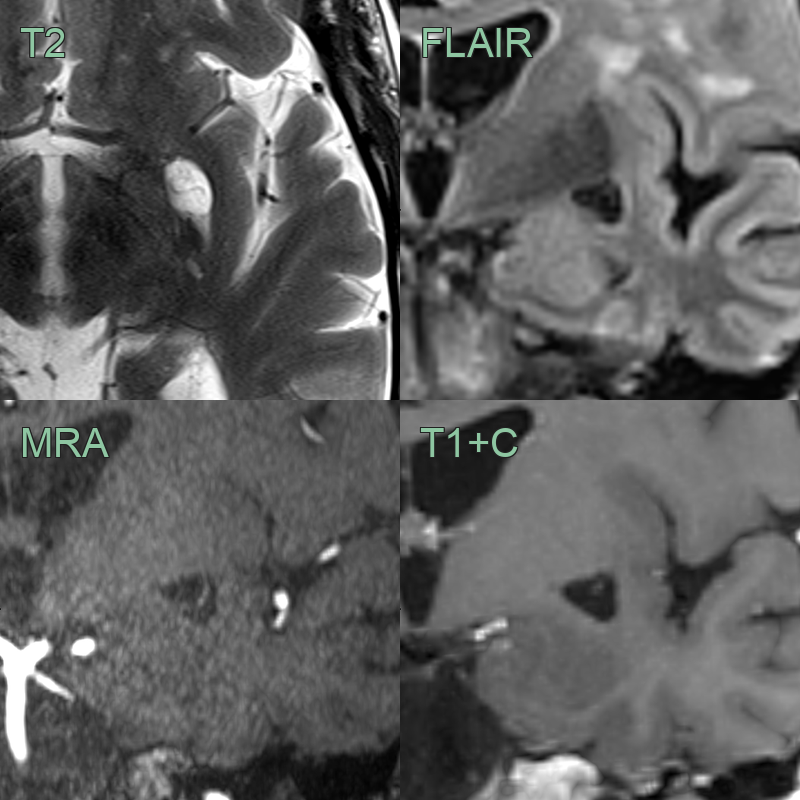

• Both T2-weighted, time-of-flight angiography and post-gadolinium T1-weighted imaging showed the vessel traversing the perivascular space.

• An incidental enlarged perivascular space in the left subganglionic region.

• The transiting artery is seens as a flow void on T2-weighted imaging.